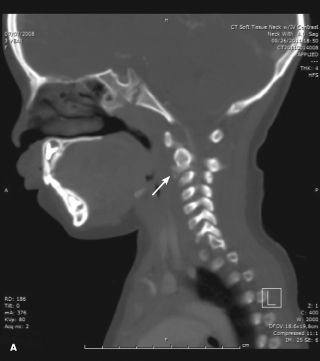

Neck Masses

Laura Sherman, MD; John W. Harrington, MD

<p><img src="/sites/default/files/transfer/1212CFP_PCCalcification_A.jpg" alt="Idiopathic Intervertebral Disk Calcification" title="Idiopathic Intervertebral Disk...